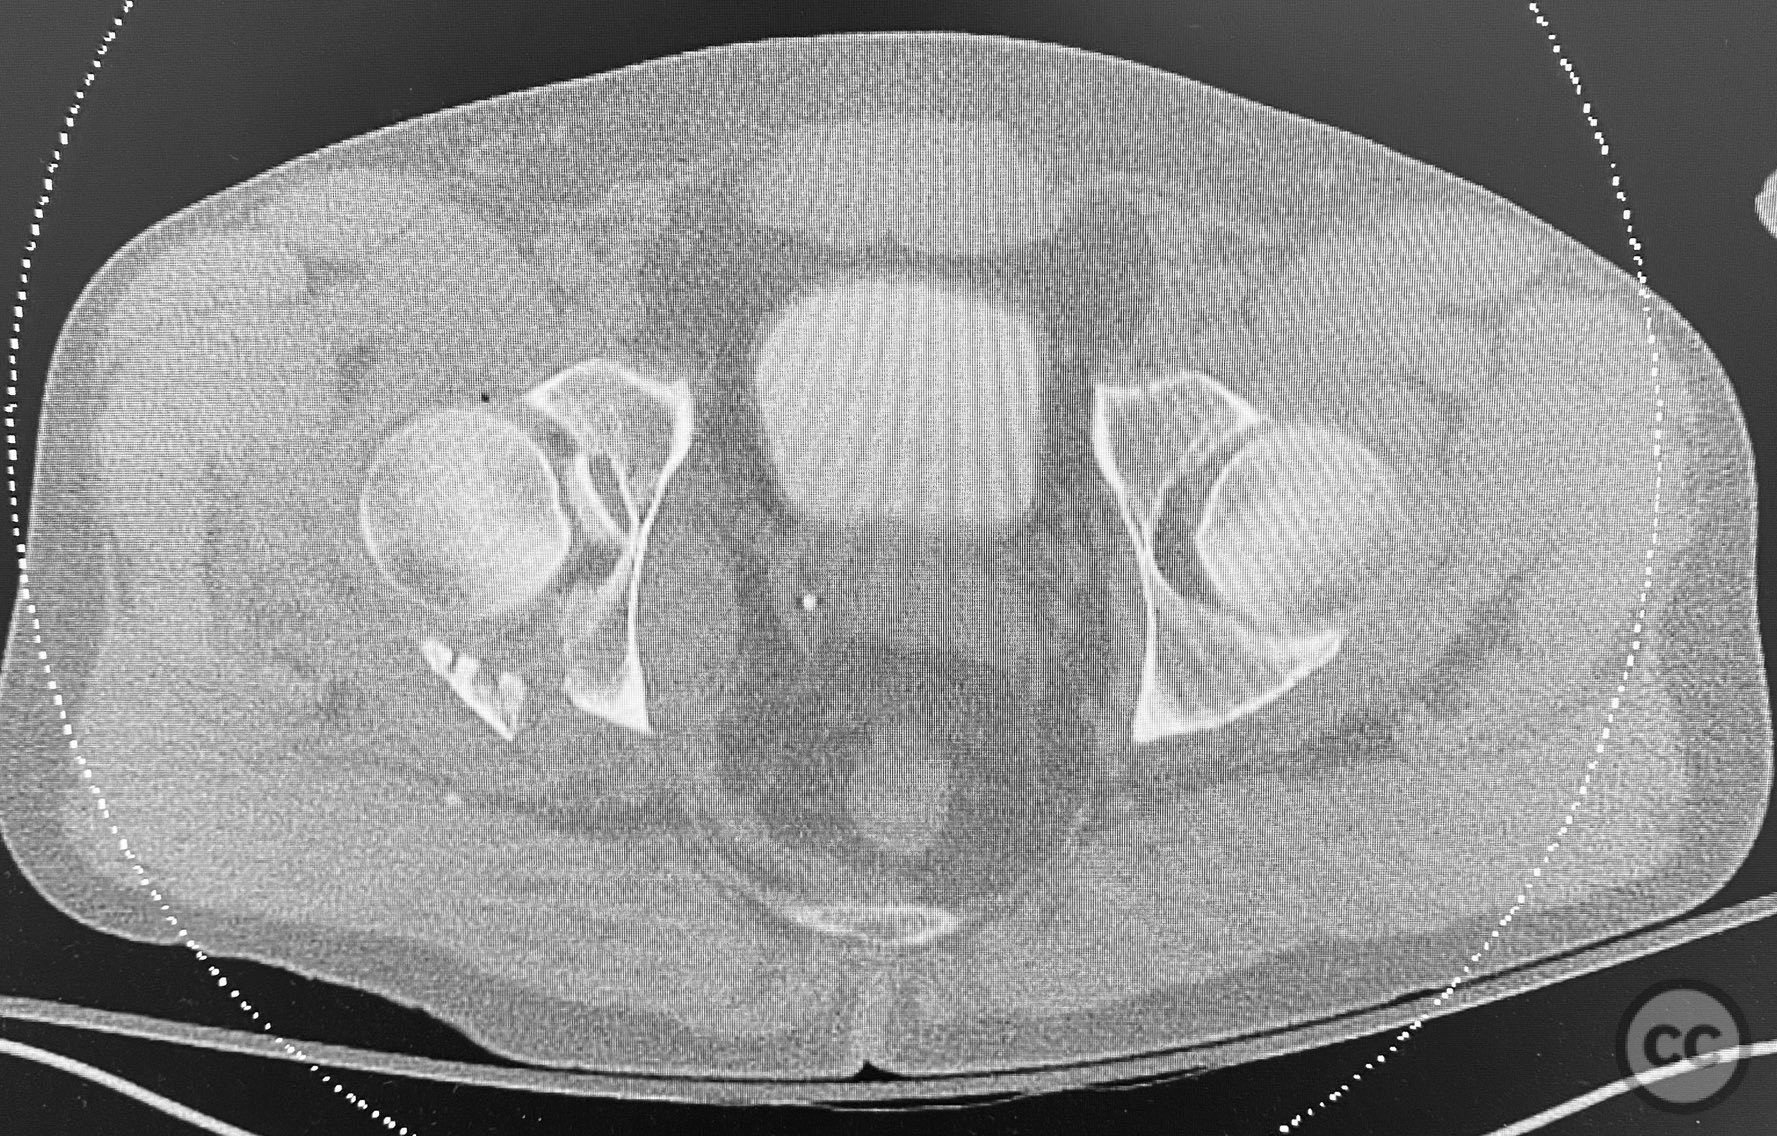

Clinical and radiological findings:  The patient sustained a comminuted acetabular fracture with multiple chondrocancellous articular fragments. The injury pattern is consistent with an AO/OTA 62-B3 (both column) acetabular fracture. Initial radiographs and computed tomography demonstrated displaced intra-articular fragments with associated segmental bone loss and wall involvement. No neurovascular compromise was documented.

Planning remarks:  The preoperative plan involved an extensile approach to the acetabulum, with the intention to carefully extract all chondrocancellous fragments for ex vivo cleansing, followed by dense packing of allograft bone grit into metaphyseal defects to support articular reconstruction. Sequential reduction of articular fragments was planned, followed by reduction and fixation of the acetabular wall using plate osteosynthesis.

All chondrocancellous fragments were meticulously removed from the wound and cleansed of hematoma and debris. Dense allograft bone grit was packed into metaphyseal defects to provide subchondral support. Each articular fragment was anatomically reduced and provisionally stabilized. The posterior wall was then reduced and definitive fixation achieved using contoured reconstruction plates. Attention was paid to restoring the congruity of the acetabular dome and maintaining anatomic reduction throughout the sequence.